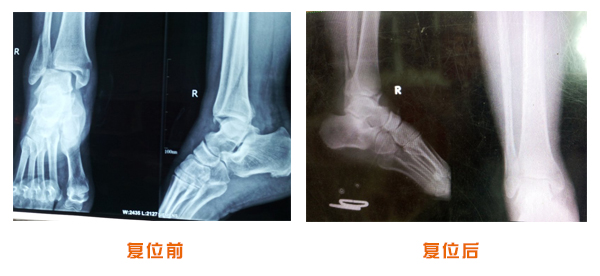

肥城市安駕莊梁氏骨科醫(yī)院是一所以梁氏手法正骨配合膏藥為特色的現(xiàn)代化??漆t(yī)院。

梁氏骨科術(shù)始創(chuàng)于清雍正年間,歷經(jīng)八代,至今已有三百年歷史。據(jù)1929年泰安縣志載“梁瑞圖先生,字增生,號蓮峰,安駕莊人,精岐黃并發(fā)明接骨,凡跌打車凡跌打車軋皮不破而碎骨者......【詳細】 |